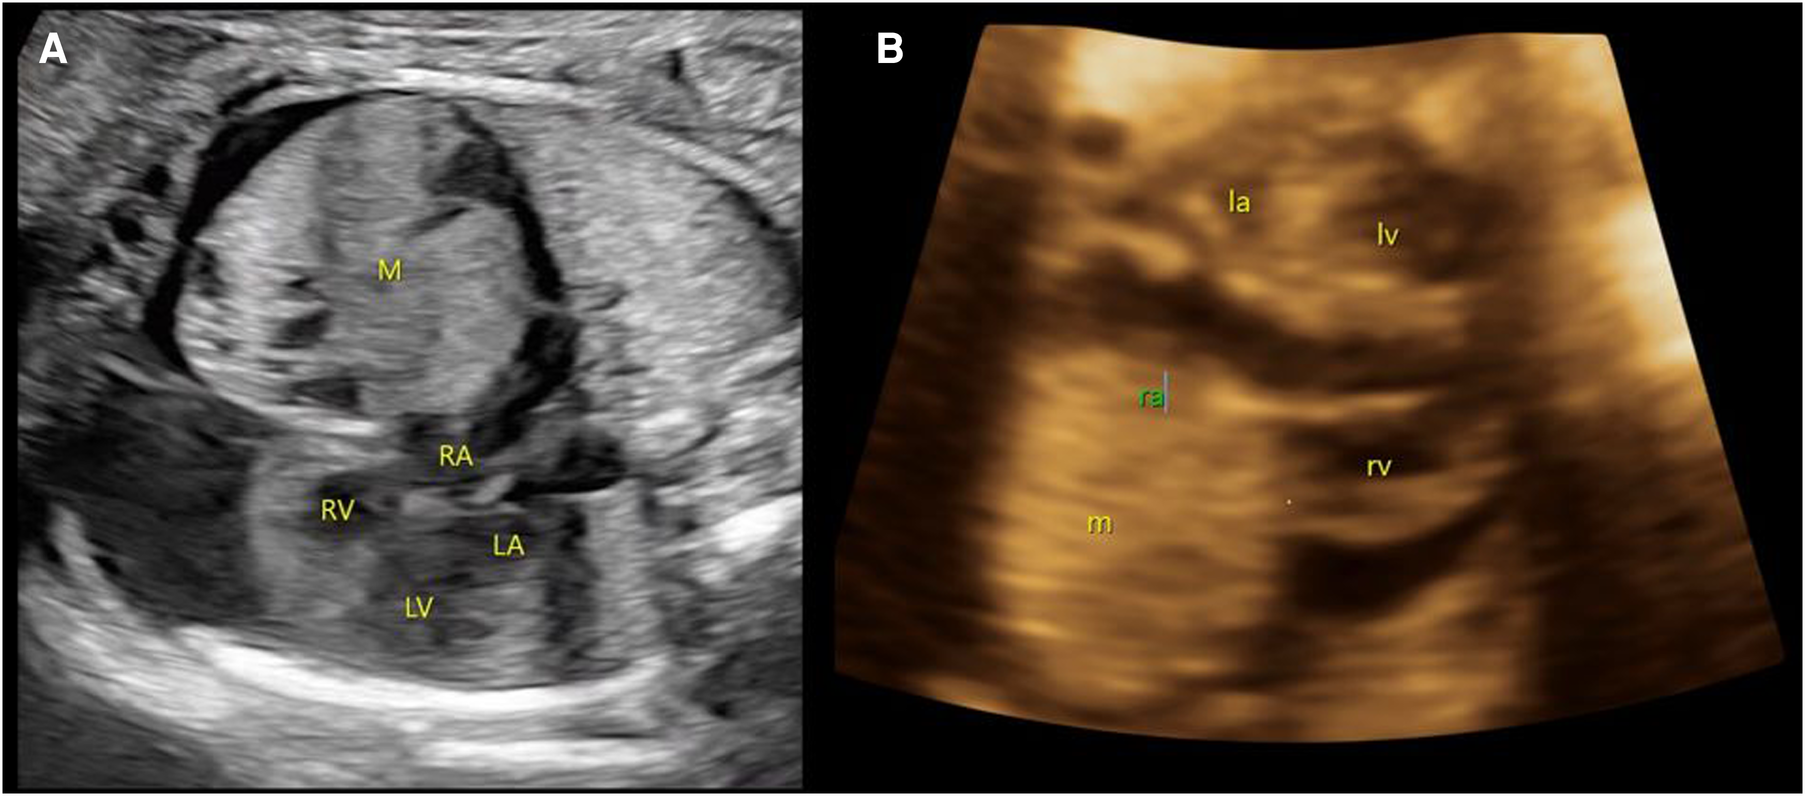

A male neonate was prenatally referred to our hospital for an anterior mediastinal mass. Four-dimensional ultrasound at 26 weeks of gestation revealed a mixed mass in the pericardium of the fetus with pericardial effusion (Figure 1). The cardiothoracic surgeon at our hospital suggested that there was no indication for prenatal intervention and recommended repeated ultrasound every other week, noting that surgery may be urgently required on the basis of echocardiogram after birth. At 37 gestational weeks, fetal echocardiography at our hospital showed a mass of approximately 37 × 36 mm in the right pericardial cavity.

Figure 1

Prenatal ultrasound images. (A) At 26 weeks of gestation, a mixed mass (M) in the pericardium of the fetus with size approximately 27 × 26 mm with pericardial effusion is demonstrated. (B) At 37 weeks of gestation, a slightly strong echo mass (m) can be seen in the right pericardial cavity, with a range of approximately 37 × 36 mm. M/m, mass; RA/ra, right atrium; RV/rv, right ventricle; LA/La, left atrium; LV/Lv, left ventricle.